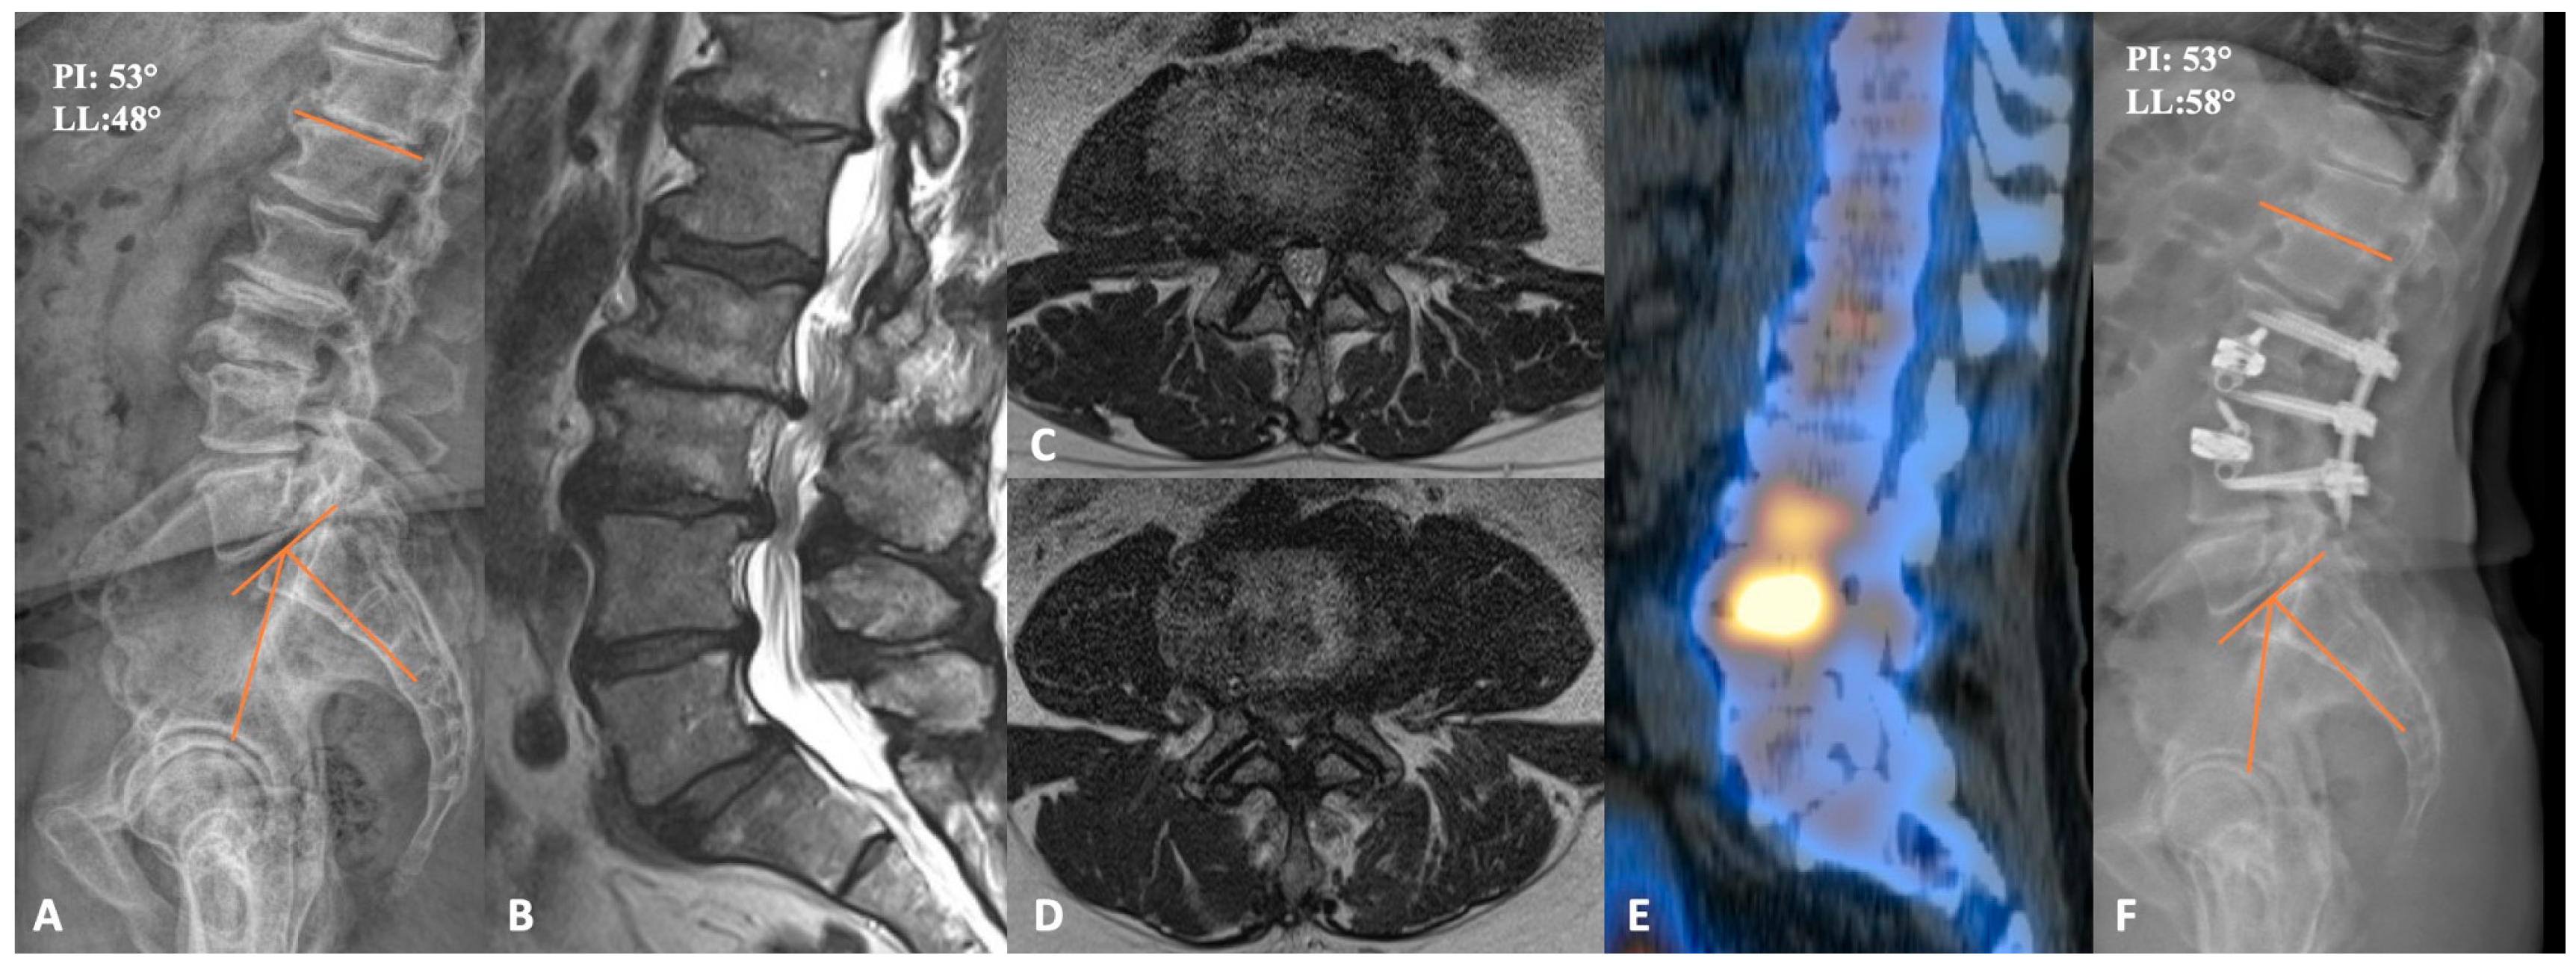

This patient was a 72-year-old-male who originally presented complaining of bilateral lateral thigh, hamstring, and low back pain for more than a year. Prior to presentation, he trialed physical therapy and epidural steroid injections at L2-3 and L3-4, which provided him with short-term pain relief. A lower-extremity neurologic exam was bilaterally unremarkable. Preoperative imaging demonstrated severe central canal stenosis at L3-L4, severe multilevel lateral-recess stenosis at L2-L3, L3-L4, and L5-S1 bilaterally, and grade 1 anterolisthesis of L5 on S1 without dynamic instability, as shown in Figure 2. CT-SPECT was also used to help understand the major pain generators. Increased uptake was seen around the disc spaces at L2-L3 and L3-L4. Importantly, there was no increased uptake in L5-S1, so it was felt that static spondylolisthesis was not a major pain generator. As the patient’s symptoms responded well to steroid injection, we decided to proceed with L2-4 PTP and posterior percutaneous fixation. The procedure was completed uneventfully in under 3 h, with a total of 100 mL blood loss. Postoperatively, the patient was discharged home on post-operative day 2 with resolution of bilateral lower-limb symptoms. Notably, lumbar lordosis increased from 48 degrees to 58 degrees, and his lower back pain gradually improved upon serial post-operative visit evaluations.

Figure 2. (A) preoperative lateral lumbar X-ray demonstrating advanced degenerative changes at L2-3 and L3-4. (B) sagittal T2-weighted MRI, together with axial cuts at L2-3 and L3-4 (C,D), respectively, showing severe central and bilateral lateral recess stenosis. (E) sagittal CT SPECT image demonstrating increased radiotracer activity at L2-4. (F) lateral lumbar X-ray of the postoperative construct with improved disc heights and lordosis. PI = Pelvic incidence; LL = Lumbar lordosis.